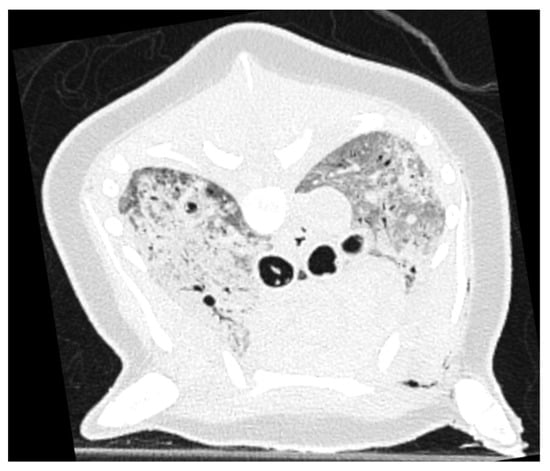

3.4. Pulmonary Parenchymal Attenuation Changes